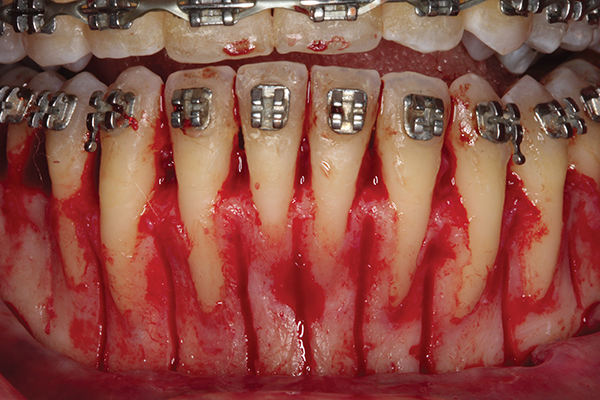

Fig 2. Full-thickness flap reflection. Note

dehiscence and fenestrations throughout. Orthodontic walls are limited to nonexistent.

Figure 2